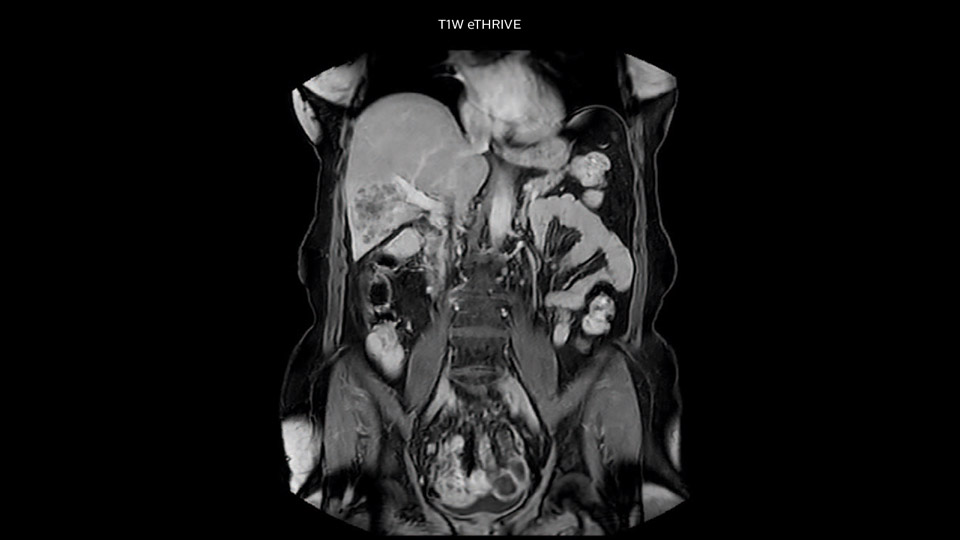

“Our liver exams are quite fast,” says Dr. Baumann. “If the patient tolerates it, we use an arms-up position to reduce the FOV and speed up the exam with dS SENSE.” “We acquire one transversal high resolution T2-weighted sequence with 3 mm slice thickness, for example for pancreas or liver lesions. Then we also add a T2 fat suppressed MultiVane XD SPIR sequence. We perform these two routinely in our liver imaging. We use high dS SENSE factors to significantly shorten scan times to 2-4 minutes, which can improve our protocol; it’s a very robust scan.” “We include mDIXON for the dynamic sequences because of the robust and homogeneous fat suppression we get with that. We had been using eTHRIVE, but we are now quite happy with mDIXON. Sometimes we use a medication to calm the bowels, to further improve the image quality.”